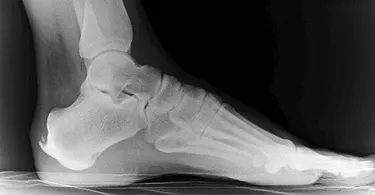

Röntgenbild Haglundextenose